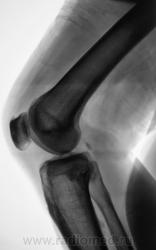

Мужчина средних лет, крепкий, ведущий активный образ жизни, занимающийся дозировано «элементами спорта», полковник милиции, в последнее время (несколько лет) почувствовал боли в области правого коленного сустава.

Снимки ниже.

Просьба высказать мнения по представленным иллюстрациям.

Энтезопатия надколенника, перегрузочная болезнь б/б кости(подозрение на неполный перелом).

Очень похожая картина на консолидированный перелом б\б кости. В проекции м\б кости определяется периостальная реакция или патологическая перестройка костной ткани.

Есть  признаки  артроза  и  синовита . Была  повреждена  передняя  крестообразная  связка.